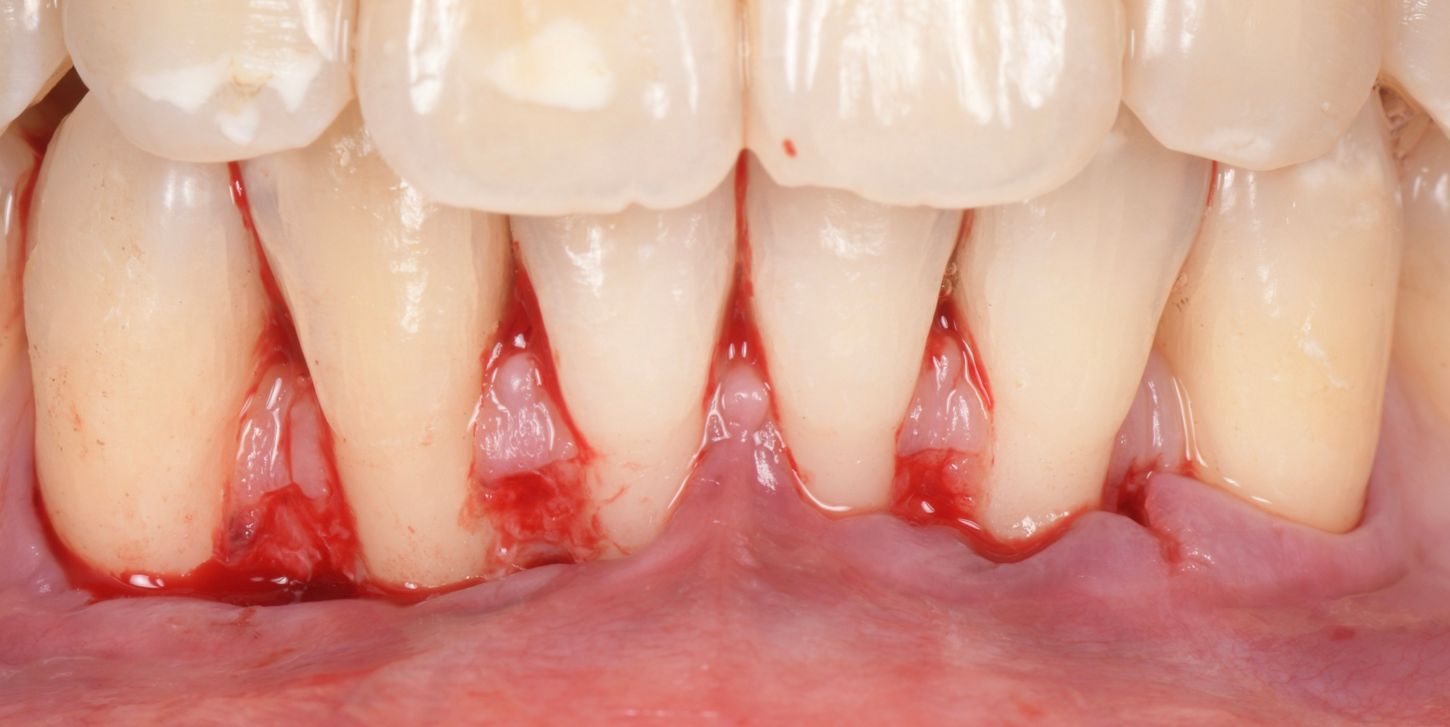

A 35-year-old female, healthy (ASA I), non-smoker, with no medication, came to our practice complaining about gingival recession and pain while brushing her mandibular incisors.

The intraoral examination revealed multiple RT 1 (Cairo 2011) gingival recessions on teeth #33 to #43, along with a thin tissue phenotype, which was associated with a traumatic toothbrushing habit (Fig. 1).